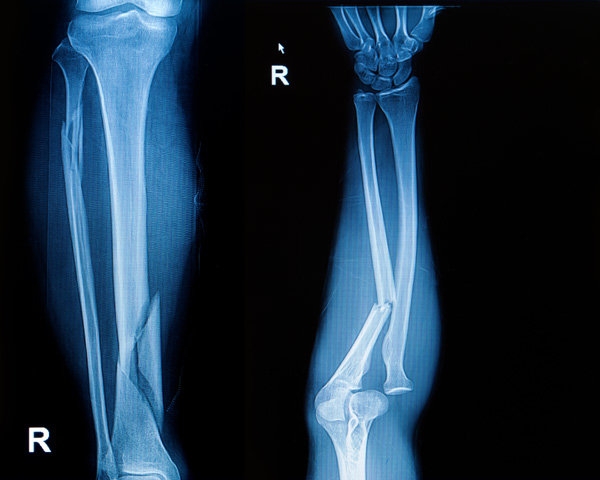

Перелом

О переломе даст знать острая боль в пострадавшей конечности, усиливающаяся при малейшей попытке пошевелить ею. Из-за этого движения становятся невозможными. Внешне конечность имеет неестественную форму из-за изменения ее оси, в результате сокращения мышц она укорачивается. При открытых переломах сомнений у вас не возникнет: всегда имеется рана, в которой иногда виден конец отломка кости.

Если есть хоть малейшие сомнения по поводу вывиха или перелома, поезжайте в травмпункт: наверняка это определить можно только с помощью рентгена. Перед поездкой к врачу важно обеспечить полный покой пострадавшей конечности, чтобы не усугубить повреждения. Так что городской транспорт — не ваш вариант доставки.